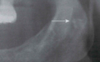

Eagle’s Syndrome (Or Stylohoid Syndrome and Carotid Artery Syndrome)

- Styloid process is a slender bony projection that originates from the inferior aspect of the temporal bone.

- It is connected to the lesser cornu of the hyoid bone by the stylohyoid ligament.

- Classic Eagles Syndrome occurs after a tonsillectomy

- Calcification

- Symptoms: vague facial pain while swallowing, turning the head, or opening the mouth. Dysphagia, dysphonia, headache, dizziness.